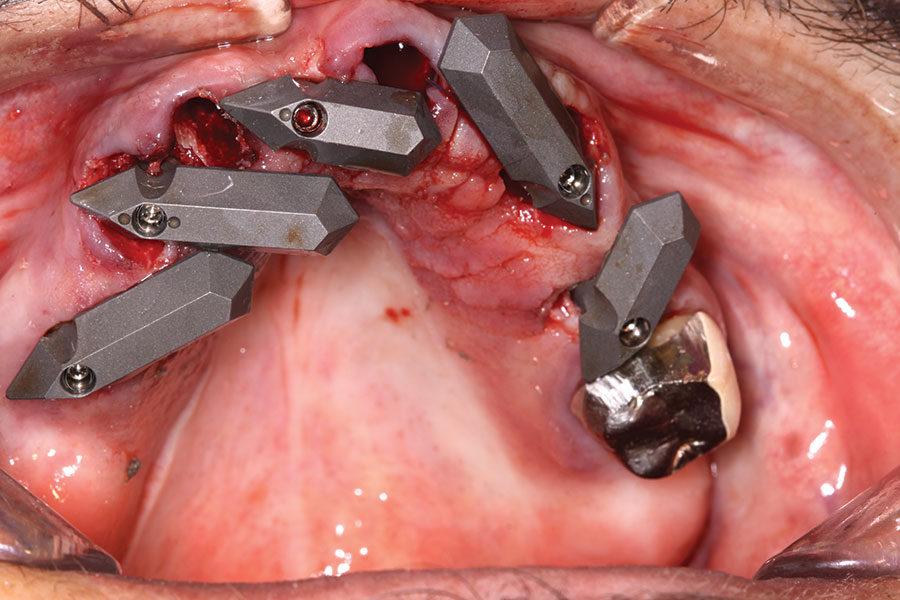

40 Ncm. Subsequently, multi-unit abutments were placed on all the implants and torqued to 30 Ncm, and scan gauges were placed on implant Nos. 8 and 11 (Figure 12 and Figure 13).

A maxillary intraoral scan was obtained with a digital scanner capturing the two remaining teeth in sites Nos. 5 and 12 and the scan gauges on implants Nos. 8 and 11. Subsequently, teeth Nos. 5 and 12 were extracted. Scan gauges were placed on implants Nos. 4, 6, and 13. At this time, another intraoral scan was captured of all the scan gauges on the five implants with the surrounding soft tissues (Figure 14 and Figure 15).

Fig 12. Partial extractions and placement of implants and multi-unit abutments.

Figure 12

Fig 13. Initial scan of scan gauges with residual teeth retained for reference.

Figure 13

Fig 14. All implants, multi-unit abutments, and scan gauges in place.

Figure 14

Fig 15. Completion of maxillary flapless immediate implant surgery and placement of multi-unit abutments.

Figure 15